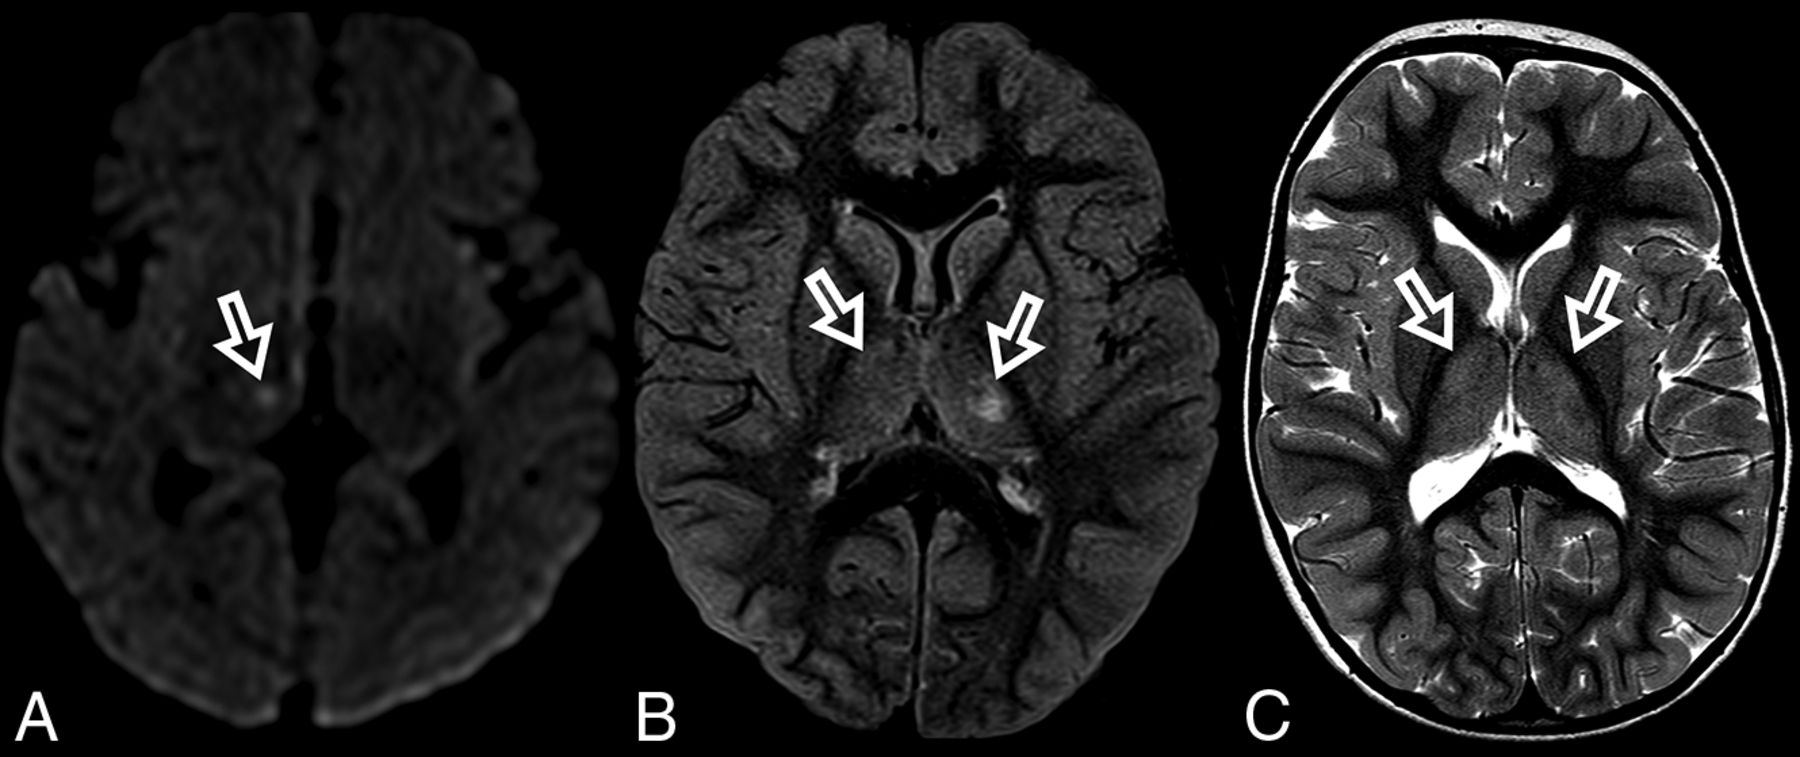

At diagnosis, brain MR imaging findings were abnormal in most patients (n = 12, 92%). The most common brain MR imaging findings were unilateral or bilateral perirolandic signal changes (n = 7, 54%) (Fig 1) and unilateral or bilateral thalamic signal changes (n = 10, 77%) (Fig 2). Perirolandic signal abnormalities were unilateral in most cases (n = 5, 71%) and were more frequently seen only affecting the precentral or both the pre- and postcentral gyri. Half of the thalamic changes were unilateral (n = 5, 50%). Simultaneous perirolandic and thalamic signal changes occurred in 6 patients (n = 6, 46%). An association of EPC (clinically/EEG) and perirolandic signal changes was present in 6 patients (n = 6, 75%), and an association of EPC (clinically/EEG) and thalamic signal changes, in 7 patients (n = 7, 87.5%). Two patients with EPC (clinically/EEG) did not present with perirolandic signal abnormalities. The findings positive for lesions overall were on the DWI of 10 patients (n = 10, 83%), on the T2WI of 9 patients (n = 9, 75%), and on FLAIR of 7 patients (n = 7, 58%). In 4 patients, DWI was the only sequence with abnormal findings. The occipital lobe was affected in the early brain MR imaging in 2 patients (n = 2, 15%). Signal changes in other brain regions were found in 5 patients (n = 5, 42%), involving multiple regions, namely the cerebral white matter, insula, putamen, caudate nucleus, fornix, cerebellar vermis, and also the frontal and occipital lobes. One patient did not present with either perirolandic or thalamic changes but instead presented with a diffuse pattern similar to that of leukoencephalopathy, with restricted diffusion in the white matter and white matter tracts (Fig 3). Three patients had an abnormally high lactate peak on MR spectroscopy. None of our patients had ASL or other perfusion-weighted imaging at the time of diagnosis. T1 and T2* imaging and SWI had negative findings at the time of diagnosis.

ADC map images of a 7-month-year old male with POLG-related disorder, demonstrating a diffuse pattern of leukoencephalopathy with restricted diffusion of the periventricular white matter of the bilateral temporal lobes in A, the occipital lobes in B, and also of the bilateral fornix in C and corpus callosum in D.

In this current study of children with POLG-RDs, all patients presented initially with seizures. Most initial brain MR imaging findings were abnormal. A temporal association between seizures and brain MR imaging abnormalities was found, suggesting lesion-related seizures. The primary brain MR imaging abnormalities included unilateral or bilateral signal changes in the perirolandic region, unilateral or bilateral signal changes in the thalamus, or a combination of the 2 in most of our patients. At diagnosis, the perirolandic region or the thalamus was spared in only 2 patients in our cohort, one with unremarkable brain MR imaging findings and the other in whom diffuse white matter with restricted diffusion was noted (Fig 3).